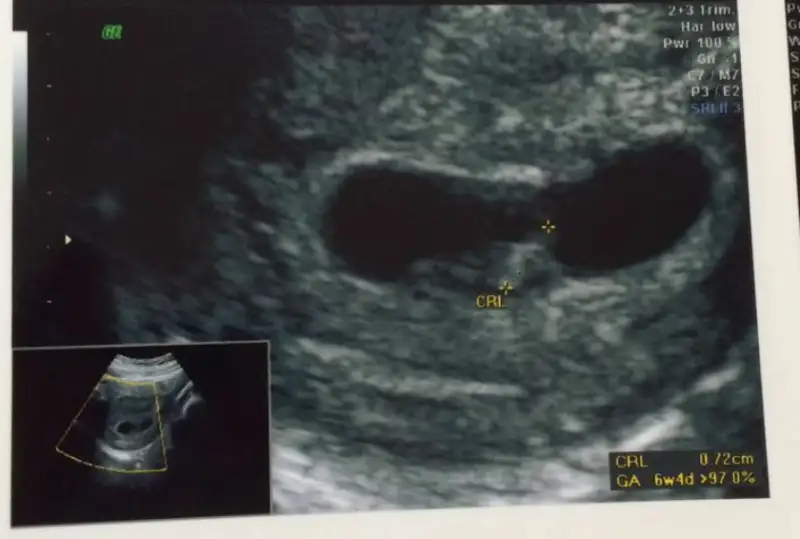

Seninki keseye gore kese fasulye seklinde ve bebis kesenin solunda vede 6 haftaya gore baya sekilli bence erkek bebis bu :))

Kese yuvarlak vede tam sagda ozaman kiz gibi canim..Canim buda 9+5 gunluk hali bi bakarmisin karindan bakti dr tekrar bi bakar misjn canjmHavalianne__

Ayy canım yaaaaa cok tesekkur ederim yerim onu ben yerimmmmm :)Seninki keseye gore kese fasulye seklinde ve bebis kesenin solunda vede 6 haftaya gore baya sekilli bence erkek bebis bu :))

Kese bayaaa bi fasulye :)) ve sola biraz daha yakin teoriye gore erkek canim :))Merve pamuk buda benim arkadaşımın canım. O da 7 hafta filan Diyör. Bunu yyorumlayabilirmisin ?